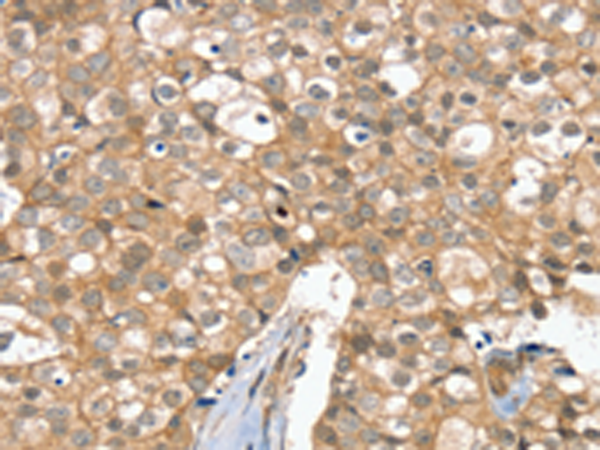

分类: 科研抗体货号: P12152别名: SSP3; Ulp1; SMT3IP1应用: IHC反应种属: Human, Mouse